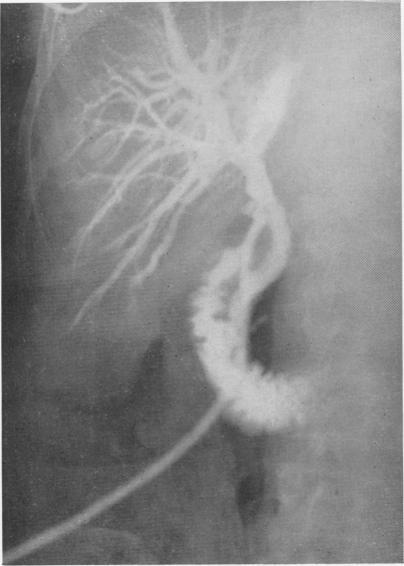

Non-surgical removal of retained common duct stones: case report.

Ann Surg. 1971 Feb;173(2):298-300. doi: 10.1097/00000658-197102000-00019.